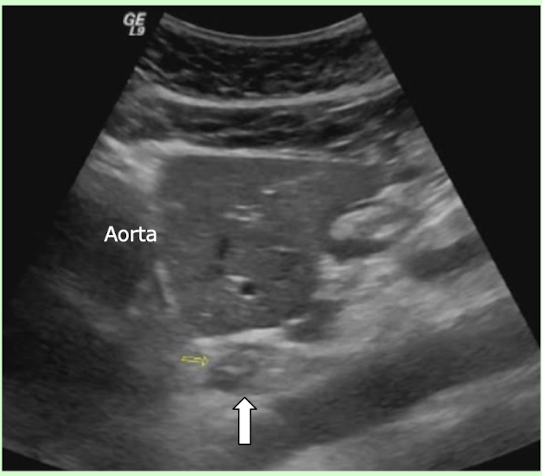

What is the arrow pointing to posterior to the left liver and anterior to the abdominal aorta?

Esophagogatric junction